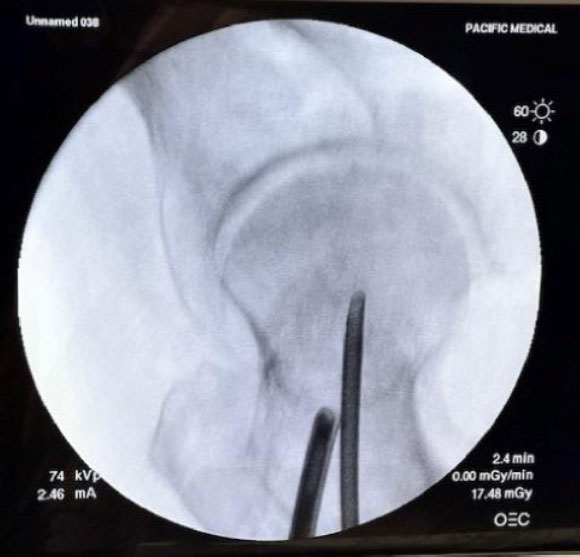

Four human cadaveric hips were examined: 86M, 82F, 77M, and one of unknown age and sex. Under plain fluoroscopy, the specimens did not appear osteoporotic. A standard arthroscope (Stryker) was used for visualization of the femoral neck intramedullary cavity. A guidewire was introduced into the femoral neck under biplanar fluoroscopy and was kept centered in both planes (Fig. 1a, b).

AP and lateral fluoroscopic views with guide wire. The starting point was above the lesser trochanter in the coronal plane.